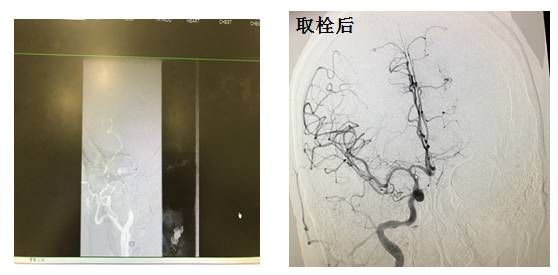

入院前数天因室速CRT-D放电一次,后患者自觉胸闷不缓解入院,第二天突发意识丧失,呼之不应,经头颅CT排除脑出血,神经系统体格检查考虑大面积脑梗,急诊行脑血管造影,并急诊取栓

颈内动脉起始段完全闭塞

发病前1天DIC报告:

APTT 28.6s(27.2-41s)

PT 12.8s(10.0-16.0)

INR 1.09

TT 60.0s↑(14-21s)

Fg 3.9g/L ↑(1.8-3.5)

纤维蛋白降解产物 1.1mg/L( < 5)

D-二聚体定量 0.57mg/L ↑( < 0.55)

♦心肌致密化不全发病率较低

♦治疗主要是针对心力衰竭、心律失常以及血栓栓塞的治疗

♦抗凝治疗意见不一,但是伴有房颤的患者建议抗凝治疗,尽管使用了正规的抗凝药物,仍不能完全避免血栓栓塞事件

♦预后差异大